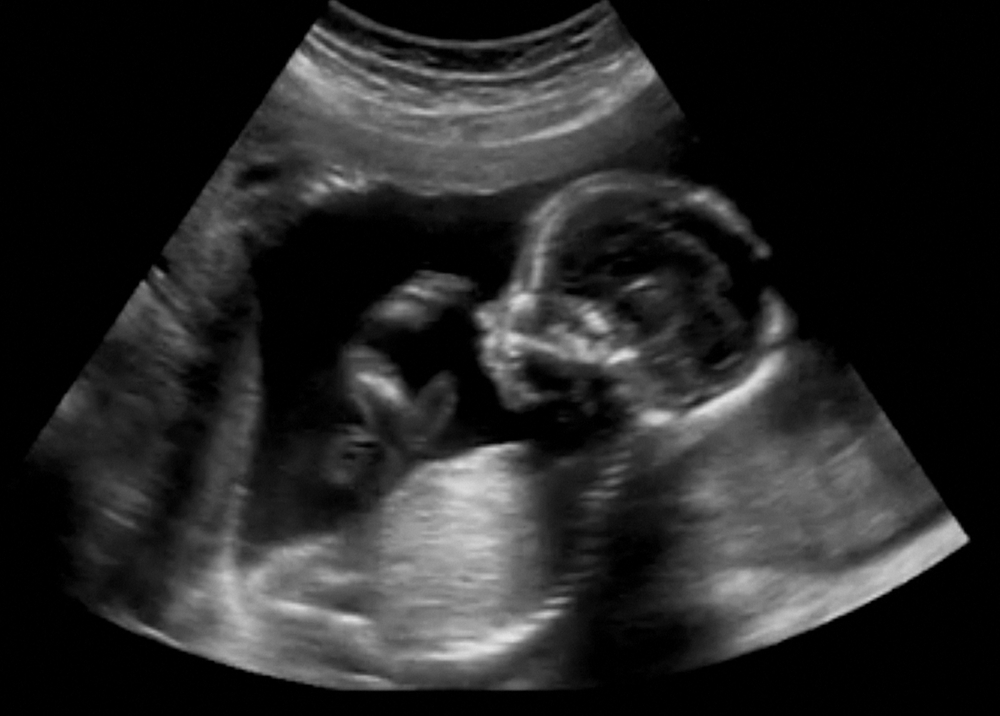

ទឹកភ្លោះ​នឹង​ចាប់​កើត​មាន​ឡើង​នៅ​សប្តាហ៍ទី១២ នៃ​ការ​បង្ក​កំណើត ហើយ​វា​មាន​ផ្ទុក​នូវ​សារធាតុ​ចិញ្ចឹម​សំខាន់ៗ អ័រម៉ូន និង​ប្រព័ន្ធ​ភាពស៊ាំ សម្រាប់​ចិញ្ចឹម និង​ការពារ​ទារក​ពី​ការ​ប៉ះ​ទង្គិច​ផ្សេងៗ។ ជា​ធម្មតា​ទឹក​ភ្លោះ​មាន​ពណ៌​ស​ថ្លា ឬ​លឿង​ស្រាល តែ​បើ​មើល​អេកូ​ឃើញ​​ទឹក​ភ្លោះ​មាន​ពណ៌​ស ឬ​ខាប់ ជា​សញ្ញា​គ្រោះថ្នាក់​ហើយ។